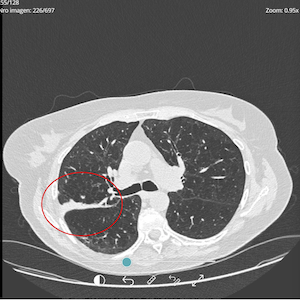

PRE-TREATMENT

OCTOBER 2024

POST-TREATMENT

SEPTEMBER 2025